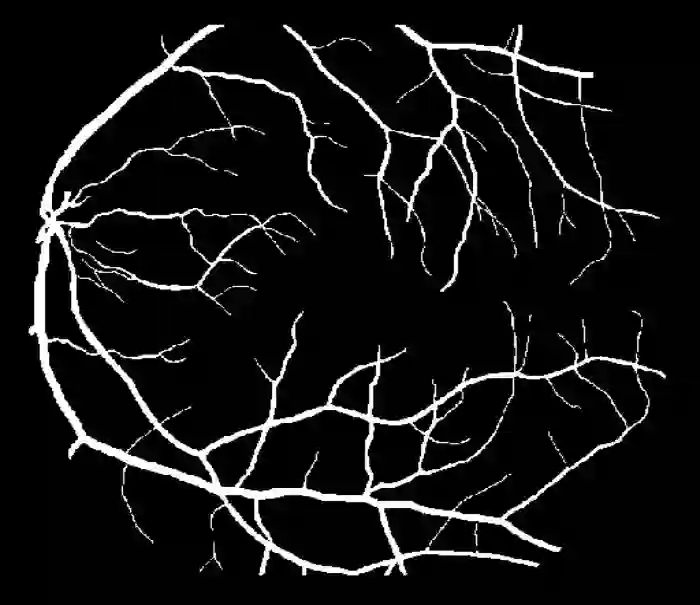

Image segmentation is a fundamental task in image analysis and clinical practice. The current state-of-the-art techniques are based on U-shape type encoder-decoder networks with skip connections, called U-Net. Despite the powerful performance reported by existing U-Net type networks, they suffer from several major limitations. Issues include the hard coding of the receptive field size, compromising the performance and computational cost, as well as the fact that they do not account for inherent noise in the data. They have problems associated with discrete layers, and do not offer any theoretical underpinning. In this work we introduce continuous U-Net, a novel family of networks for image segmentation. Firstly, continuous U-Net is a continuous deep neural network that introduces new dynamic blocks modelled by second order ordinary differential equations. Secondly, we provide theoretical guarantees for our network demonstrating faster convergence, higher robustness and less sensitivity to noise. Thirdly, we derive qualitative measures to tailor-made segmentation tasks. We demonstrate, through extensive numerical and visual results, that our model outperforms existing U-Net blocks for several medical image segmentation benchmarking datasets.

翻译:图像分割是图像分析和临床实践的一项基本任务。 目前的最先进的技术基于U- shape 类型编码器- 编码器网络,称为U- Net。 尽管现有的 U-Net 类型网络报告了强大的性能,但它们受到若干重大限制。 问题包括: 接收字段大小的硬编码, 影响性能和计算成本, 以及它们没有考虑到数据中固有的噪音。 它们与离散层有问题, 没有提供任何理论依据。 在这项工作中, 我们引入了连续的 U- Net, 一个图像分割网络的新组合。 首先, 持续的 U- Net是一个连续的深神经网络, 以第二顺序普通差异方程式为模型, 引入新的动态区块。 第二, 我们为我们的网络提供理论保证, 显示更快的趋同性、 更高强度和较少对噪音的敏感度。 第三, 我们通过广泛的数字和视觉结果, 我们通过模型超越了现有的一些医学图像分割基准数据集的 U-Net 。